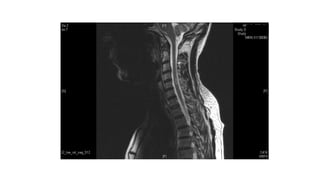

Spinal Lesions

cord lesion

30 year old female, presented 2009 with paraesthesia hands

and lower limbs, intermittent symptoms since, had 2 children

since, no physical signs……